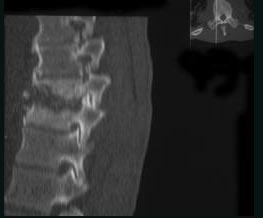

问题 女,59岁,腰背部疼痛伴低热,乏力,请结合影像学检查,选出最可能的诊断 ( )

选项 A、椎体压缩骨折 B、强直性脊柱炎 C、化脓性脊柱炎 D、脊椎结核 E、脊柱转移瘤

答案 D